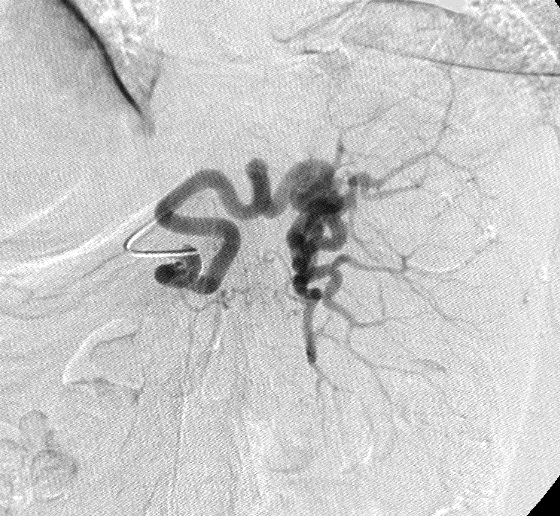

困难的病例:Tortuosity Preventing Selective Catheterization病例 1:70岁 男 转移性结直肠癌。脾亢,血小板减少症影响进一步化疗

Selective Catheterization for PSE 随访